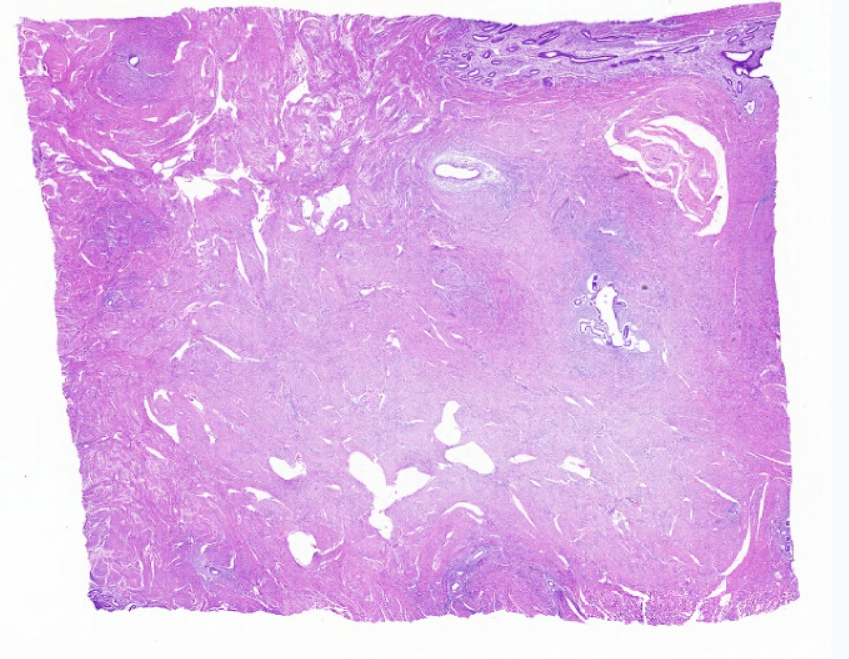

低倍镜:区分卵巢的皮质及髓质,皮质有不同时期发育的卵泡分布于其中,髓质为结缔组织及丰富的血管构成。着重观察皮质内不同发育阶段的各级卵泡及闭锁卵泡、黄体和卵泡间的结缔组织。高倍镜:重点观察各级卵泡。

1.全景图

2.被膜

3.皮质

4.原始卵泡

5.初级卵泡

6.次级卵泡

8.成熟卵泡

9.卵母细胞